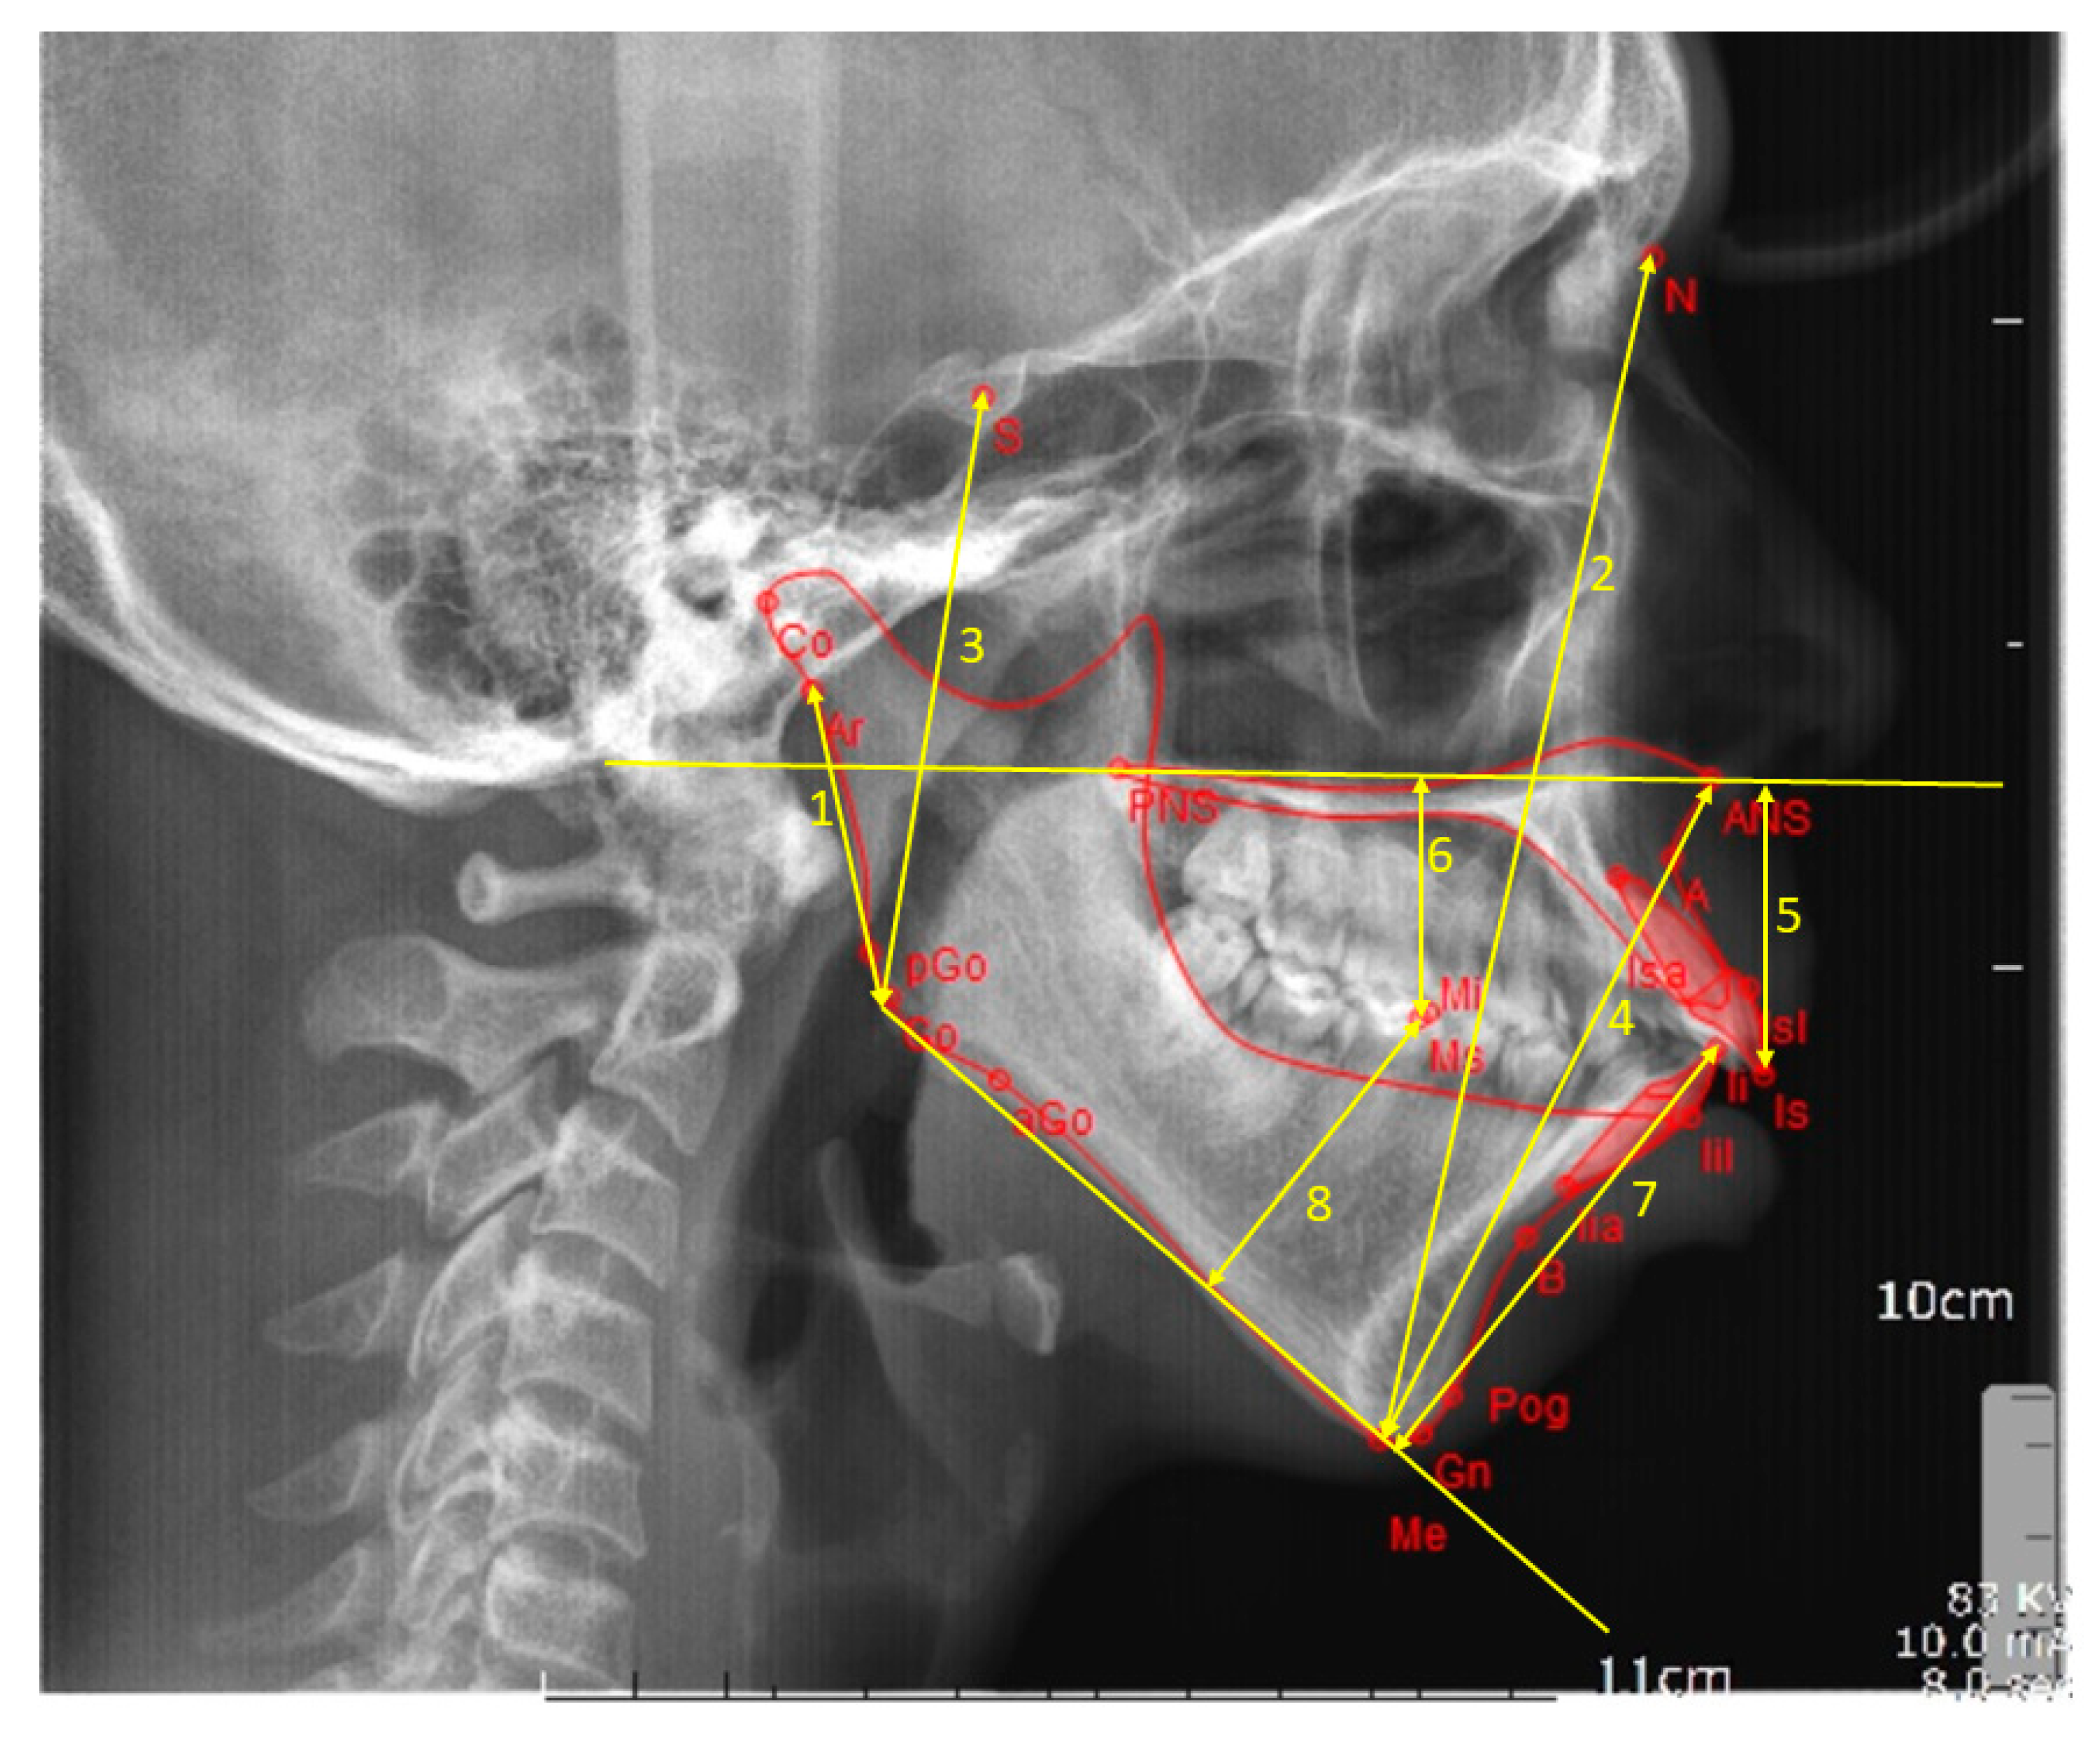

Figure 2.

Linear cephalometric measurements. 1 = ramus height, 2 = anterior facial height, 3 = posterior facial height, 4 = lower anterior facial height, 5 = upper incisor to maxillary plane, 6 = upper molar to maxillary plane, 7 = lower incisor to mandibular plane, and 8 = lower molar to mandibular plane.